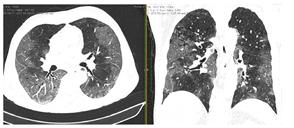

2. Наличие клинических проявлений, указанных в п. 1, в сочетании с характерными изменениями в легких по данным компьютерной томографии (КТ) (см. Приложение 1 настоящих рекомендаций) вне зависимости от результатов однократного лабораторного исследования на наличие РНК SARS-CoV-2 и эпидемиологического анамнеза.

- Изменения при КТ (рентгенографии), типичные для вирусного поражения (объем поражения минимальный или средний; КТ 1-2)

- Изменения в легких при КТ (рентгенографии), типичные для вирусного поражения (объем поражения значительный или субтотальный; КТ 3-4)

- Изменения в легких при КТ (рентгенографии), типичные для вирусного поражения критической степени (объем поражения значительный или субтотальный; КТ 4) или картина ОРДС.

КТ имеет высокую чувствительность в выявлении изменений в легких, характерных для COVID-19. Применение КТ целесообразно для первичной оценки состояния ОГК у пациентов с тяжелыми прогрессирующими формами заболевания, а также для дифференциальной диагностики выявленных изменений и оценки динамики процесса. КТ позволяет выявить характерные изменения в легких у пациентов с COVID-19 еще до появления положительных лабораторных тестов на инфекцию с помощью МАНК. В то же время, КТ выявляет изменения легких у значительного числа пациентов с бессимптомной и легкой формами заболевания, которым не требуется госпитализация. Результаты КТ в этих случаях не влияют на тактику лечения и прогноз заболевания при наличии лабораторного подтверждения COVID-19. Поэтому массовое применение КТ для скрининга асимптомных и легких форм болезни не рекомендуется.